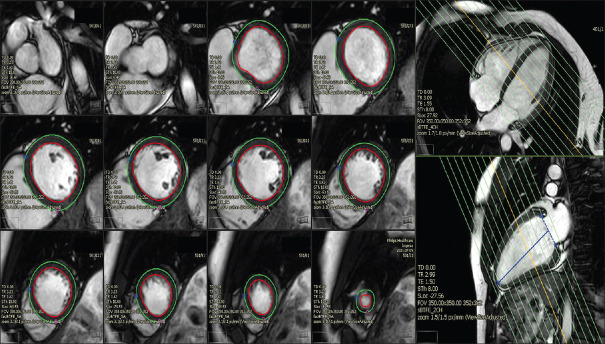

Methods: Twenty volunteers were scanned with HHE, standard echocardiography (SE), and CMR. LVEF and SV were measured with each modality, and their accuracy and precision were evaluated.

Abstract Image